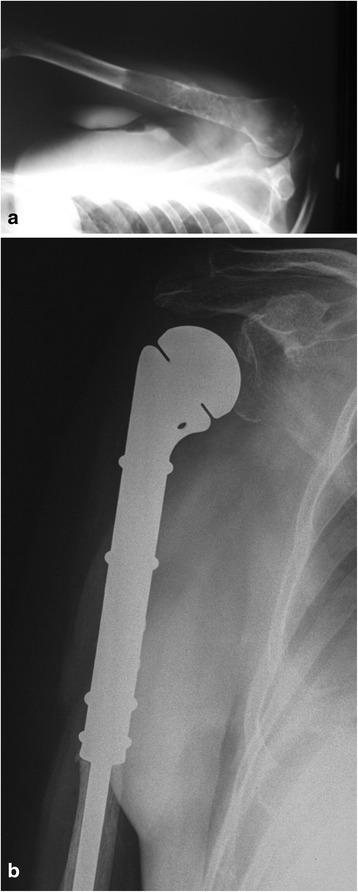

Breast, prostate, and lung cancers are the most common primary tumors that metastasize to bones. The most common site of the lesions is the proximal femur; sporadically, they do occur in bones distal to the knee and elbow. After the surgery, all the patients could walk, most of them without crutches. The pain, rated on a VAS scale, decreased significantly, and the Karnofsky score improved. We observed that joint mobility and the strength of the muscles in the limbs allowed for normal functioning. Postoperative complications including infections and local tumor recurrences were rarely observed.

CONCLUSIONS

The use of modular prostheses is an adequate method of treatment in patients with bone metastases. A radical resection of the tumor, which prevents local recurrences and loosening of implants, gives good outcomes. Reduced joint mobility resulting from muscle attachment cutting is well tolerated and concerns mainly patients that underwent operations on the humerus.

使用模块化假体是治疗骨转移瘤患者的一种适当方法。肿瘤的根治性切除可防止局部复发和植入物松动,效果良好。因切断肌肉附着而导致的关节活动度降低耐受性良好,主要影响接受肱骨手术的患者。